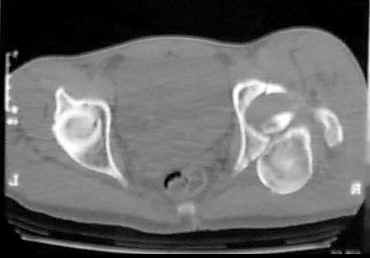

21 YO male who sustained a transverse and posterior wall fracture of the left acetabulum, with a entrapped fragment.

Closed reduction was not possible